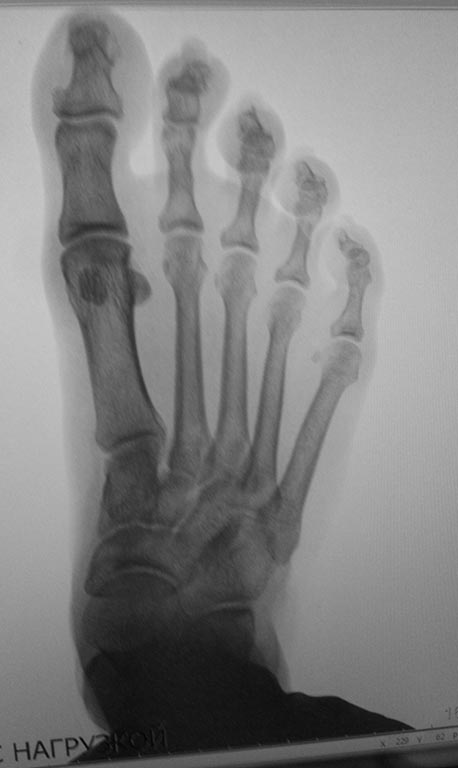

Обратилась женщина с жалобами на выраженную боль, натоптыши в области

проксимальных межфаланговых суставов V пальцев стоп.

У больной имеется деформация Тейлора ( угол М4М5 11.5 с двух сторон под

нагрузкой). В области пятого плюснефалангового сустава деформация. Боли,

гиперемии нет.

Достаточно ли в данном случае остеотомии пятой плюсневой кости с

нормализацией угла М4М5 и укорочением?